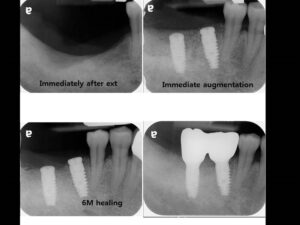

Етапи імплантації зубів

Імплантація зубів – процедура, що вимагає суворого дотримання встановленого протоколу лікувально-діагностичних заходів, що включає кілька етапів імплантації зубів. Кількість і характер етапів імплантації можуть відрізнятися в залежності від початкового стану зубощелепного апарату пацієнта, а також обраного виду і методики проведення самої процедури установки імплантів – одно або двоетапної.

Двоетапна методика є найбільш надійною і прогнозованою, вона відрізняється дуже високими показниками приживлюваності імплантатів (97-98%), а встановлені з її використанням штучні зуби можуть прослужити 15-20 років, а нерідко і довше. Процедура встановлення дентальних імплантів по двоетапній методиці можна виділити 3 основних етапи імплантації:

На цьому етапі імплантації здійснюється установка самого імпланту і формувача – перехідника між кореневою частиною імпланта і його супраструктурами. Таким чином, в хірургічному етапі можна виділити два проміжних етапу імплантації:

При використанні класичної двоетапної методики імплантації спочатку встановлюється сам імплант і лише після його повного і остаточного приживлення на ньому через перехідник (формувач) фіксується супраструктура – коронка або міст. Проміжок між цими двома етапами імплантації становить кілька місяців.

Десна надрізається по гребеню альвеолярнго відростка і відшаровується слизисто-окисний клаптик, щоб створити необхідне поле для роботи хірурга-імплантолога. Далі за допомогою фрез різного діаметру (від меншого до більшого) висвердлюється канал потрібного діаметру і глибини – формується кісткове ложе для штучного кореня. У це ложе встановлюється імплант на необхідну глибину: гвинтові конструкції вкручуються, циліндричні встановлюються незначною натяжкою.

Коли імплант встановлений, в нього вкручують заглушку, яка захищає його від механічних впливів, а також запобігає інфікуванню кісткового ложе і проростання тканин в отвір для гвинта. Після цього слизисто-окисний клаптик укладається на своє колишнє місце, а розріз щільно зашивається. На цьому перший хірургічний етап імплантації закінчується.

Далі йде «перерва», необхідна для надійного приживлення імпланта. Кісткова тканина нижньої щелепи, більш щільна і об’ємна, для цього потрібно 2-3 місяці, в менш щільній губчастій кістці верхньої щелепи він приживається 4-6 місяців.